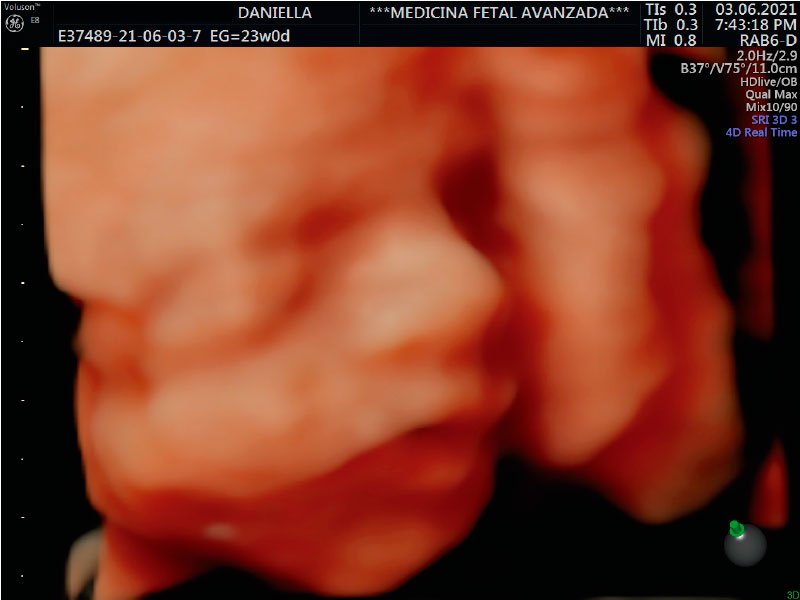

Ahora estamos en la semana 24 de este par de mellizos que esperamos recibir en septiembre.